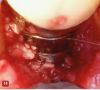

Fig 9. The VMIS procedure for peri-implant bone loss incorporates the removal of a thin piece of connective tissue that has been in direct contact with the implant in the area of bone loss. The removal of this tissue is similar to the harvesting of a connective tissue graft and is shown in the photograph (arrow). This is done to remove microscopic foreign bodies of cement and/or titanium particles that are associated with peri-implantitis.

Figure 9